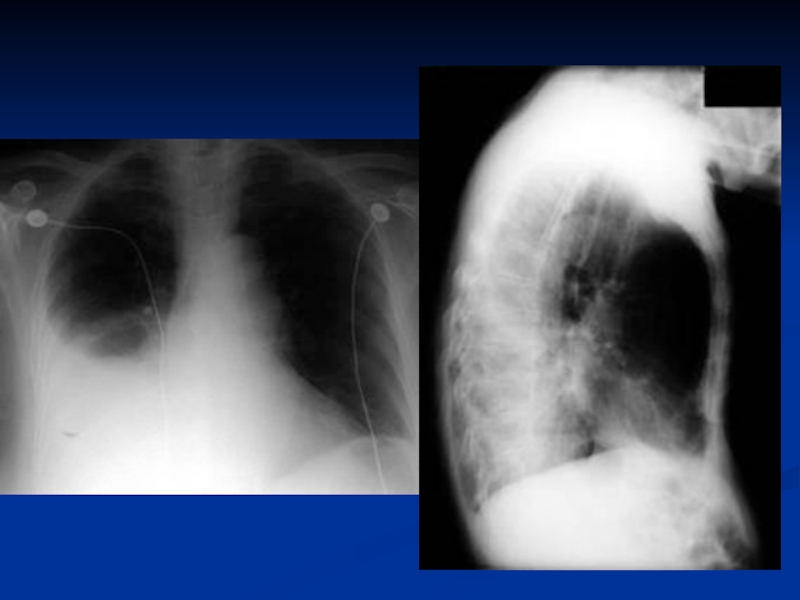

рентгенограмма: инфильтраты легочной ткани, усиление легочного рисунка в перифокальных участках.

нарушение терморегуляции (гипер- или гипотермия, токсикоз);жесткое бронхиальное или ослабленное дыхание, через 3-5 дней присоединяются влажные хрипы;укорочение перкуторного